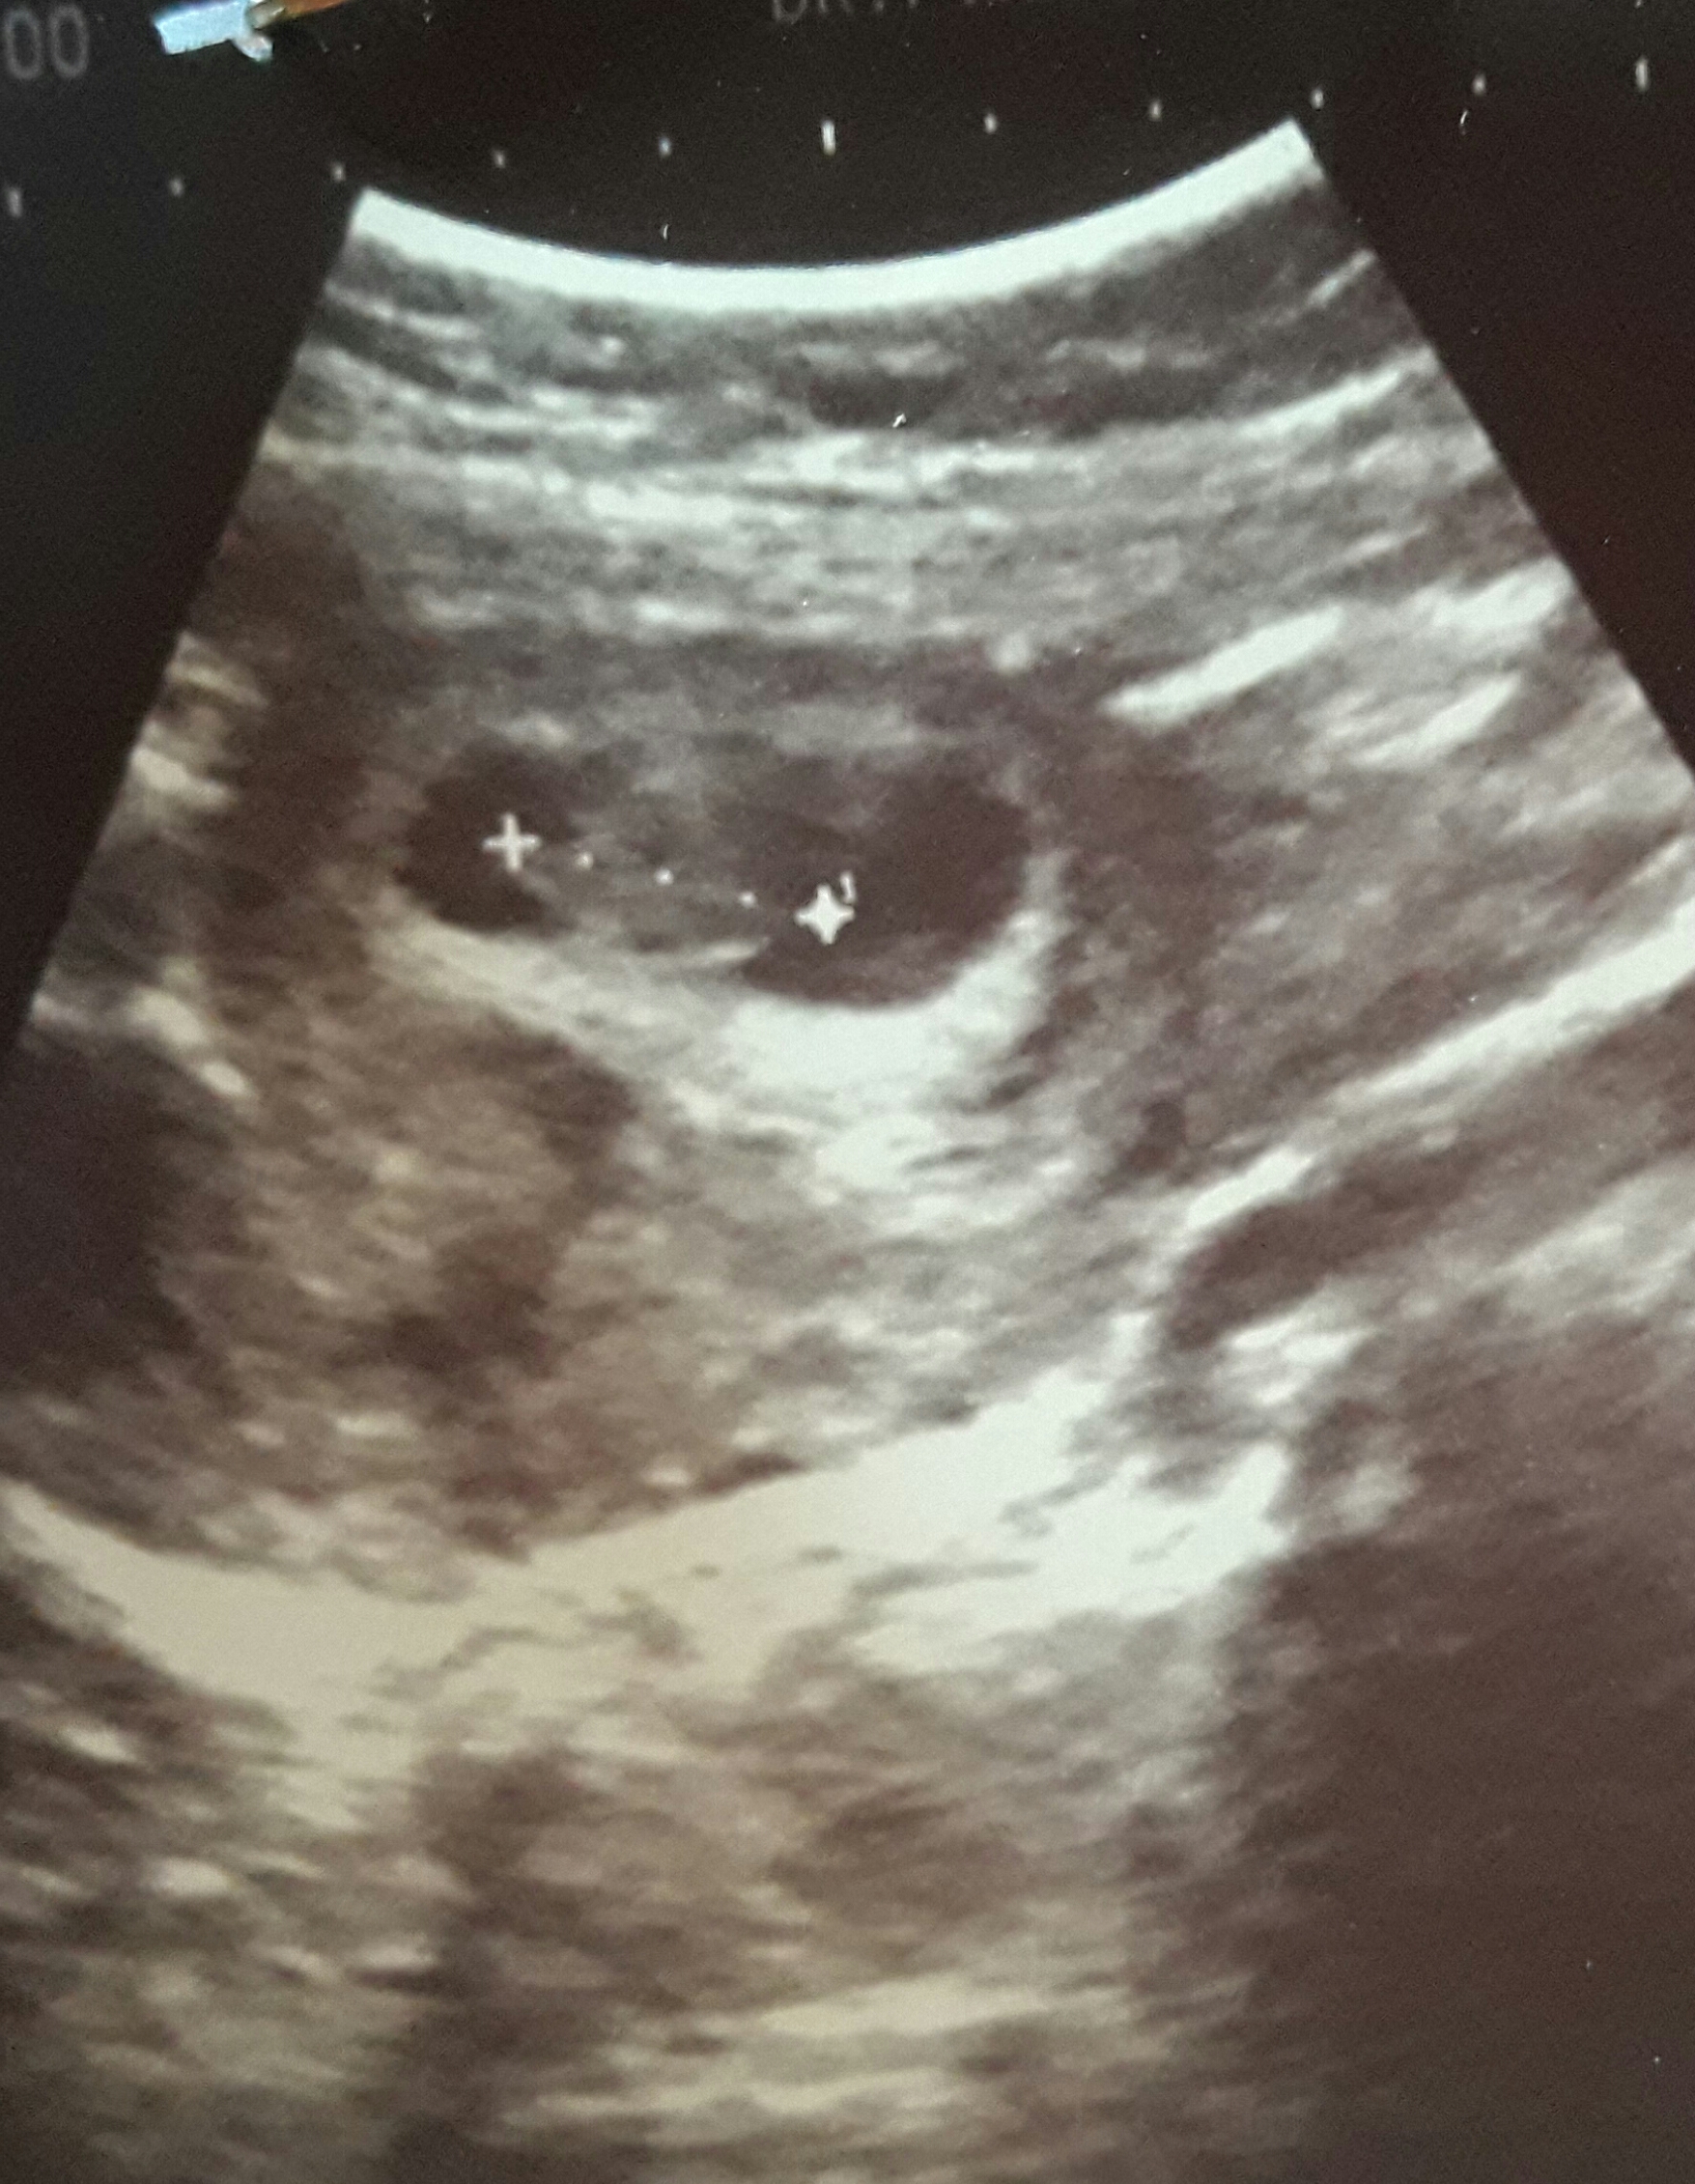

برای من اینم درست بود سنوی هشت، نه ، هفته اگه جنین طرف راست باشه دختره اگه طرف چپ باشه پسره، عکس سنو ...

فکر کنم نظریه رمزیه اسمش، اگه تو عکس سنو هشت، نه هفته جنین طرف راست باشه دختر طرف چپ باشه پسر، من سنوگرافی پسرم هم نگه داشتم، هر دو رو دیدم برای مت درست بود

اره منم شنیدم ولی نمیفهمم این بچه من کجاس! وسطه؟؟

بچم سمت راسته